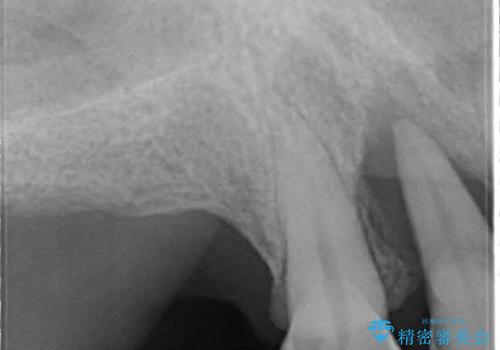

歯周病におかされた前歯の再建治療

- 歯周病により欠損が生じた歯槽骨、まずは再生治療をおこなう

→治癒後、確定外科を行い完全に歯周ポケットを除去し、最終的に歯周補綴をおこなう